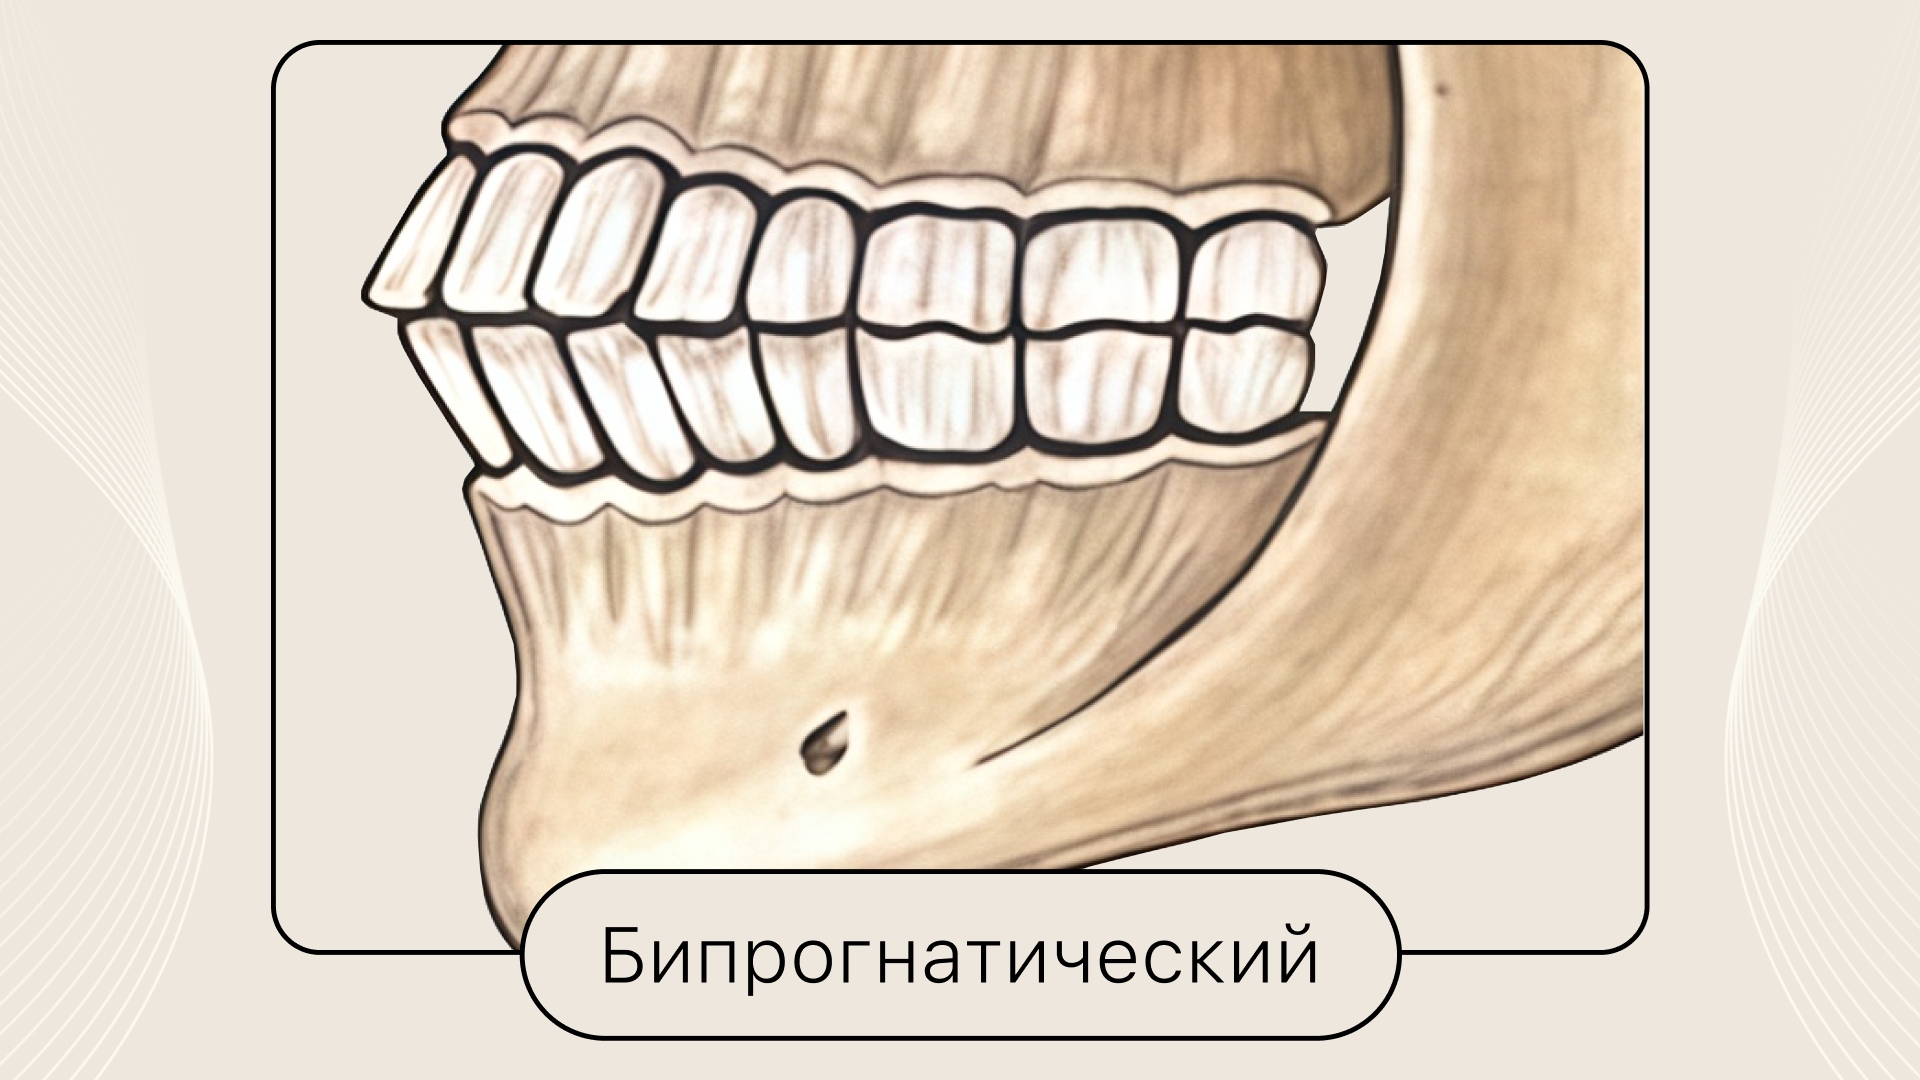

Бипрогнатический

Верхние и нижние передние зубы слегка наклонены вперёд, боковые зубы смыкаются как при ортогнатическом прикусе.